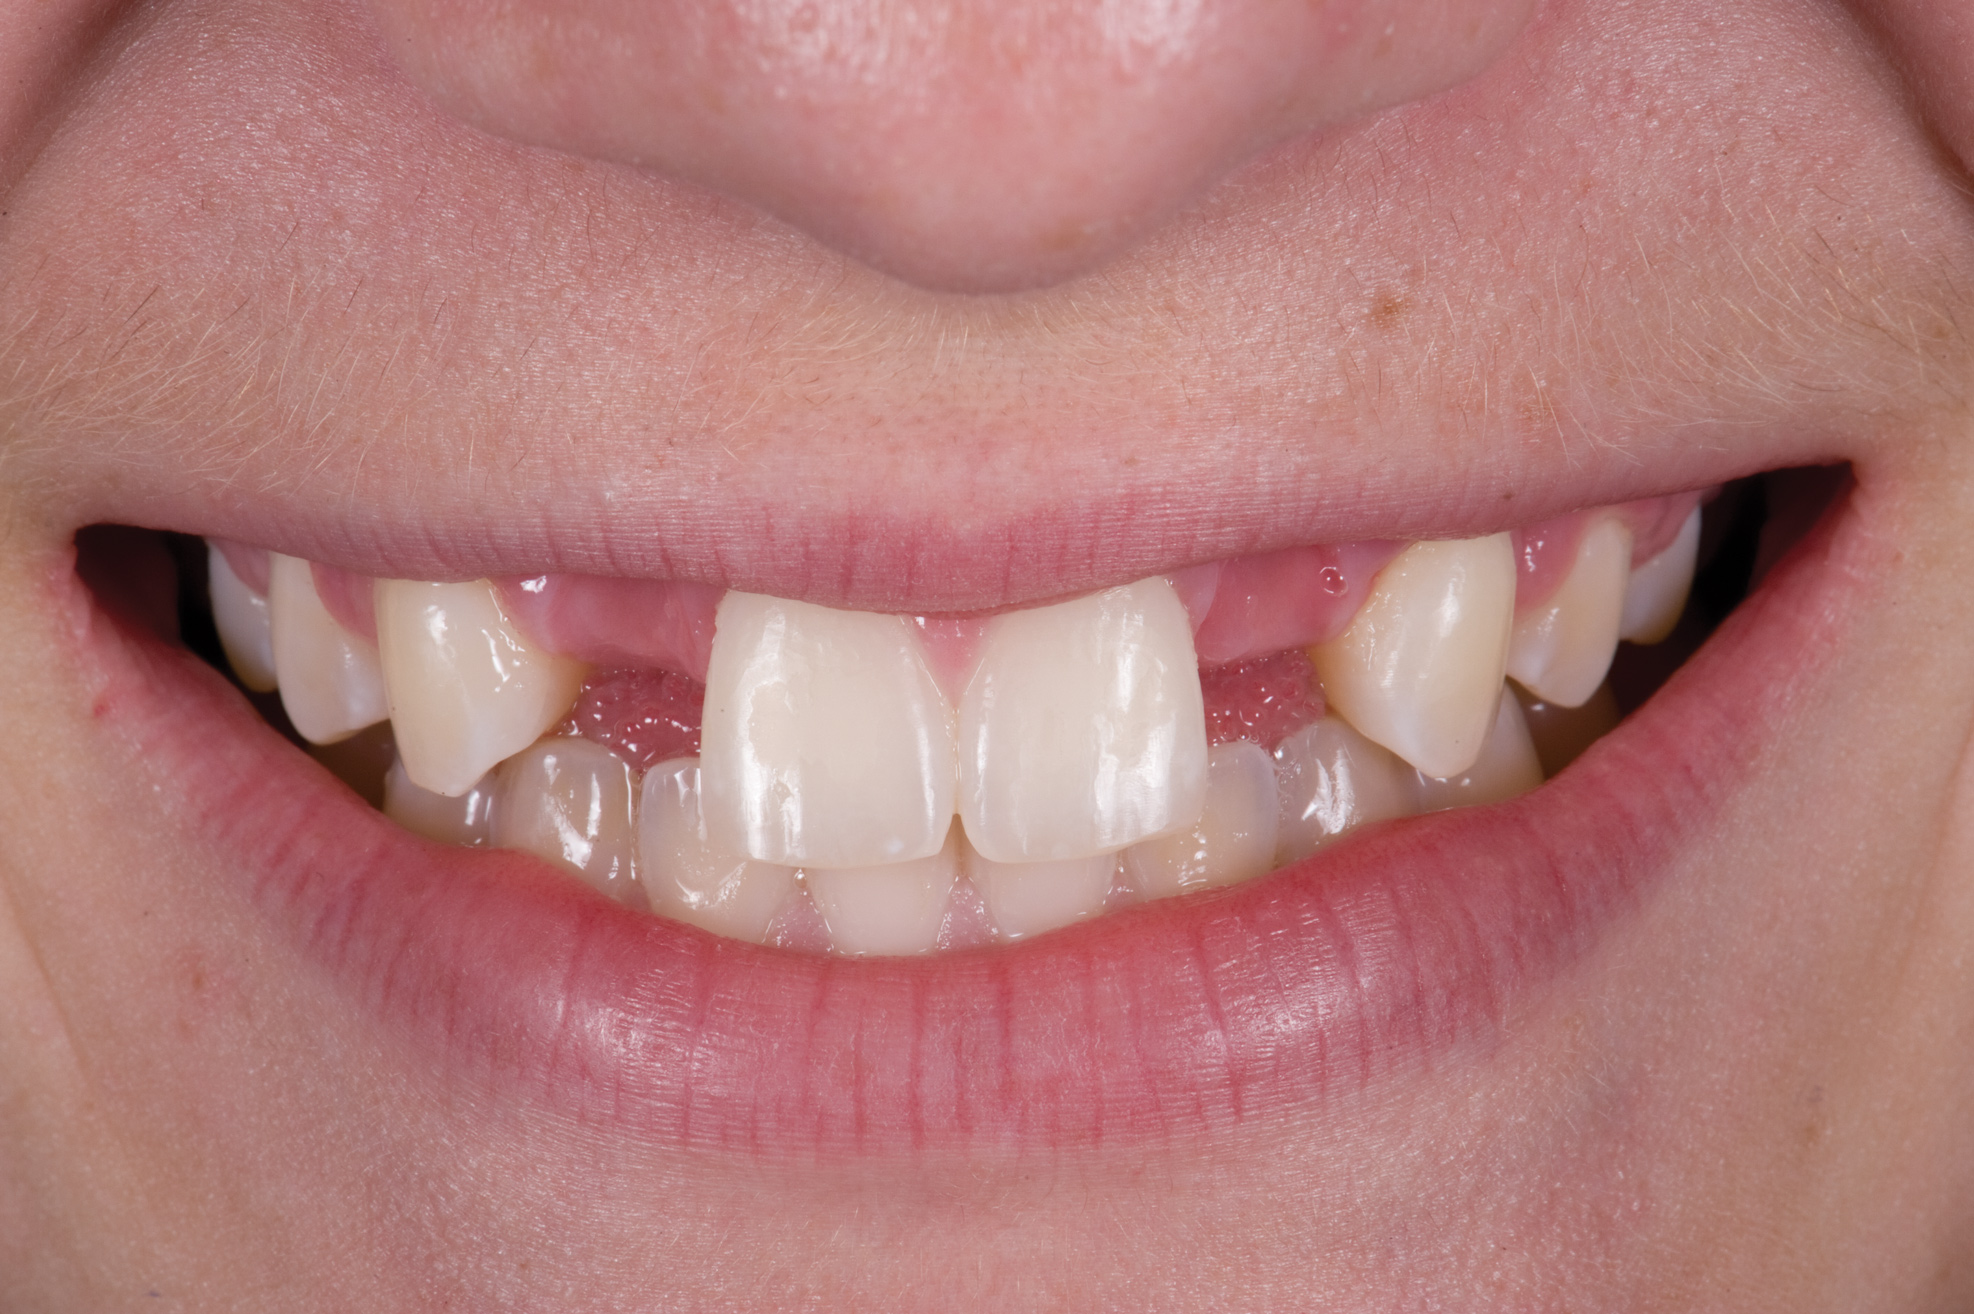

A 14-year-old patient presented to the office with his mother (Figure 1). His chief complaint involved the large spaces between the teeth created by his missing right maxillary lateral incisor and his small left maxillary lateral incisor. He desired to replace the missing tooth with an implant and create a beautiful smile. Upon examination, he was found to have a Class I canine and molar relationship, but because he had a tooth size/arch size discrepancy and space distal to the right central incisor, the remaining incisors had drifted to the right. The left maxillary lateral incisor was peg-shaped and in a cross bite position. Studies have shown a clear association between congenitally missing teeth and reduced tooth size.59-62 Because he was only 14-years-old at the time and could not have implants placed until the cessation of growth (around 22 years old), he was sent to the orthodontist for alignment of the teeth.16,17

Fig 1. Initial presentation. Note midline shift to right, missing right lateral incisor, and diminutive left lateral incisor in crossbite.

Figure 1